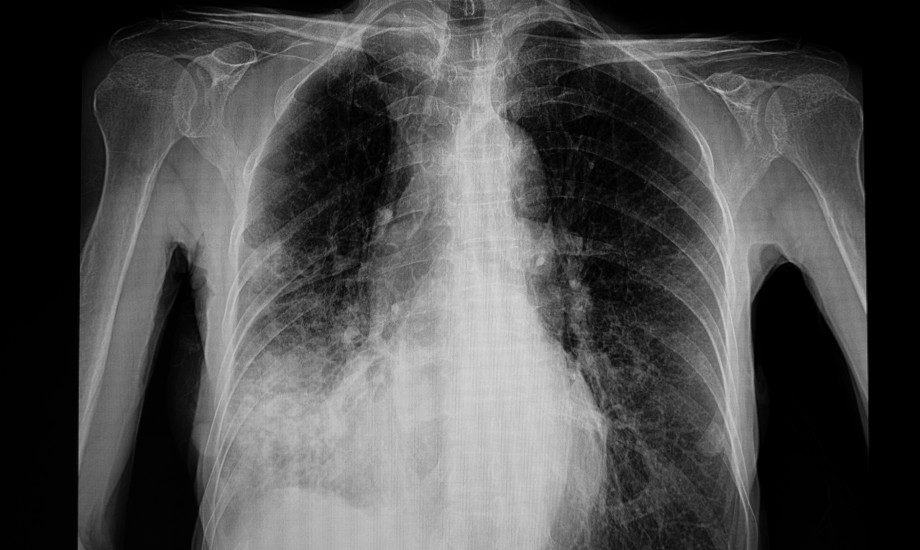

Was steuert Entscheidungen bei kindlicher Lungenentzündung?

Bei Verdacht auf eine Lungenentzündung entscheiden Ärztinnen und Ärzte oft über Röntgenbild und Antibiotika. Eine neue Studie zeigt, welche Befunde diese Schritte auslösen und wo Praxis und Theorie auseinandergehen.